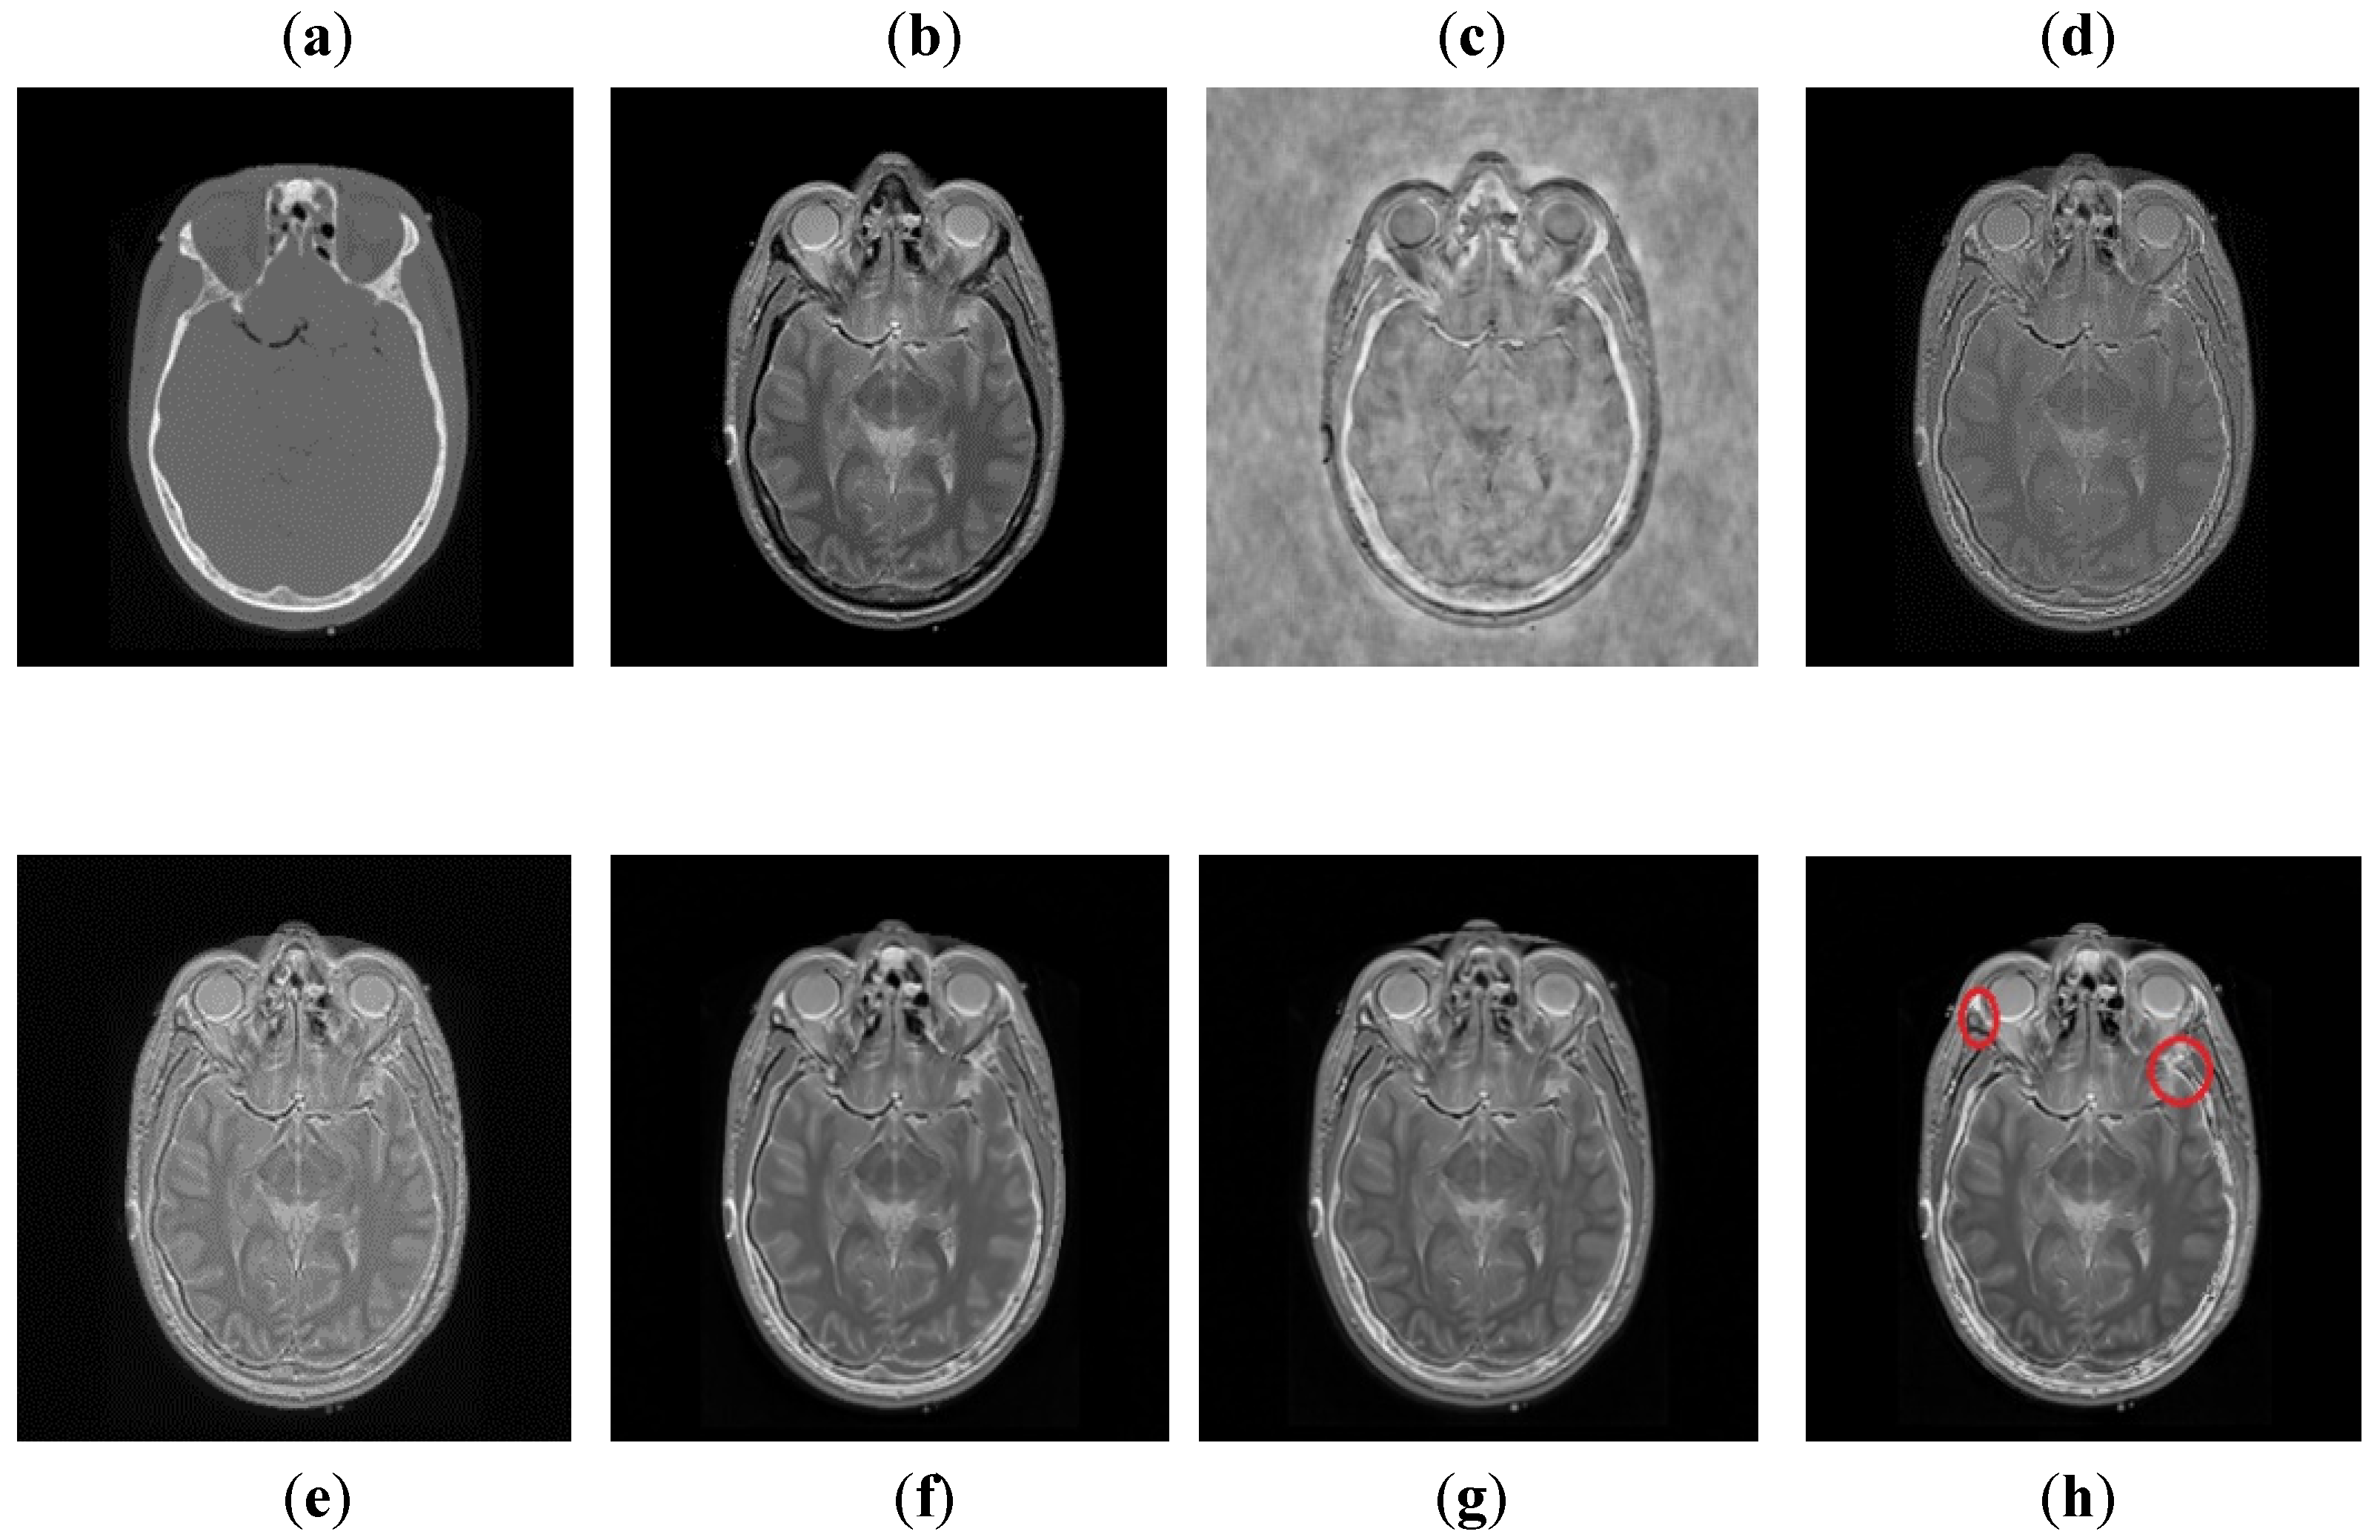

It can be depicted in Figure 8 that the DCT method contains most of the information from the CT image, but it fails to obtain more information from the MRI image. The DWT and NSST-SF-PCNN produce images with good contrast, but both methods cannot obtain more information about edges. The CSR method has better results than DCT, DWT, and NSST-SF-PCNN by producing less noise and good contrast images. However, this method also fails to capture more information about soft tissues. The CNN scheme and proposed method produce better results with uniform illumination, but it can be observed in red boxes that the proposed method can capture more information about edges and soft tissues and preserve whole useful information. Additionally, the proposed method effectively retains the complete information from both source images.

Figure 8. Data-2: (a) CT image, (b) MRI image, (c) DCT, (d) DWT, (e) NSST-SFT-PCNN, (f) CSR, (g) CNN, and (h) Proposed.